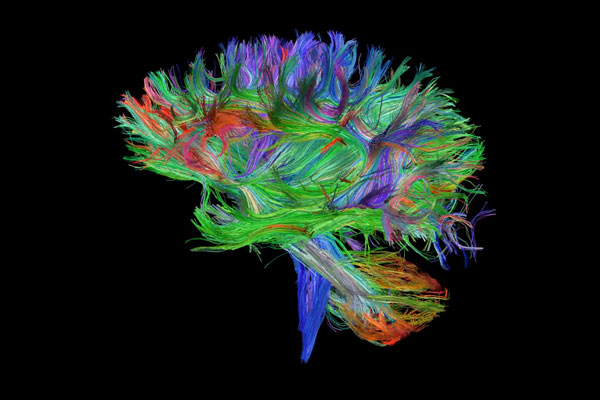

Building Brain Pathways (Video)

Bonus Prize Winner

Brenton Hordacre

School of Health Sciences

This series of images comes from our current stroke study looking at a treatment to enhance recovery of arm function. We use magnetic resonance imaging (MRI) scans to tell us several pieces of information about the brain and how it has been affected by stroke. This particular set of images tells us about the brain’s pathways (the coloured lines). Each of the lines in this image represent an individual brain pathway. We are primarily interested in a bundle of pathways called the corticospinal tract which is the vertical blue/purple lines seen in the video that connect to the spinal cord. This pathway carries commands that control movement of our arms. Having a functional corticospinal tract is an important factor in recovery from stroke.